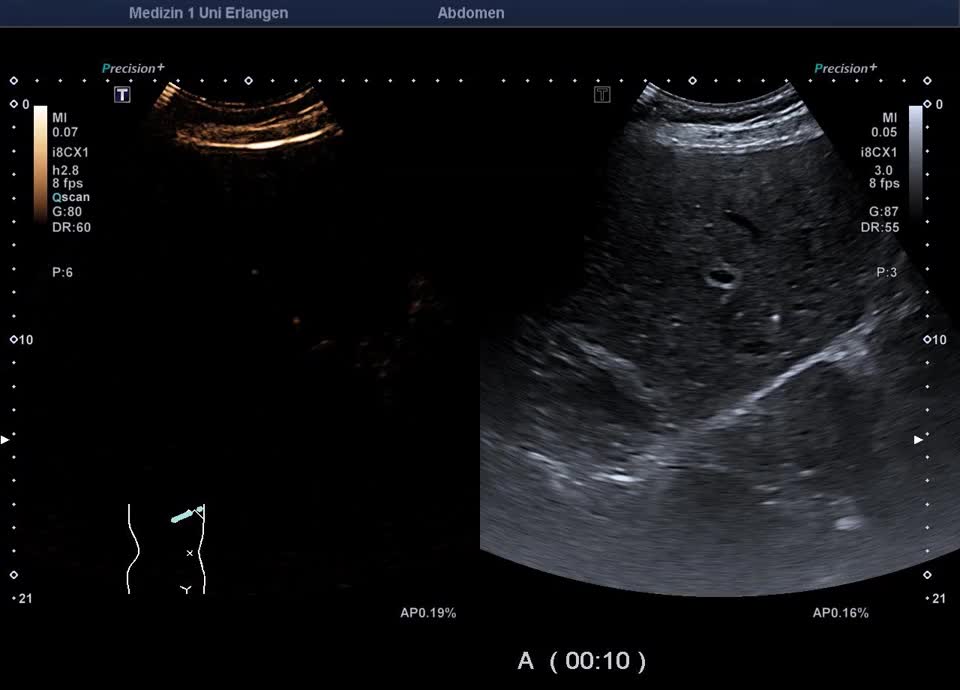

Kasuistik: 66-jähriger Patient mit seit der Jugend bekannter γ-GT-Erhöhung, sonographische Vorstellung zum Ausschluss eines cholangiozellulären Karzinoms. Sonographisch zeigt sich im B-Bild ein inhomogenes Leberparenchym mit diffus verteilten kleinen Kometenschweifartefakten im rechten Leberlappen. Das sonographische Bild ist vereinbar mit multiplen biliären Hamartomen (Von-Meyenburg Komplexe). Sie bestehen aus Zysten, die mit Gallengangsepithel ausgekleidet sind, und Bindegewebe, treten einzeln oder multipel auf und weisen typischerweise eine Größe von etwa 0,5–15 mm auf. Sonographisch stellen sie sich als echoreiche Noduli dar. Zum Ausschluss malignitätsverdächtiger Herdbefunde wurde eine kontrastmittelverstärkte Sonographie durchgeführt. Im CEUS zeigt das Leberparenchym in der portalvenösen und Spätphase homogenes Enhancement – die echoreichen Noduli sind isokontrastiert (Ausschluss Malignität). Die kleinen Zysten sind in allen Perfusionphasen nicht KM-aufnehmend. In Zusammenschau der Bildgebung und der bekannten γ-GT-Erhöhung besteht kein Anhalt für eine maligne Lebererkrankung. Eine einmalige sonographische Verlaufskontrolle wurde vereinbart.